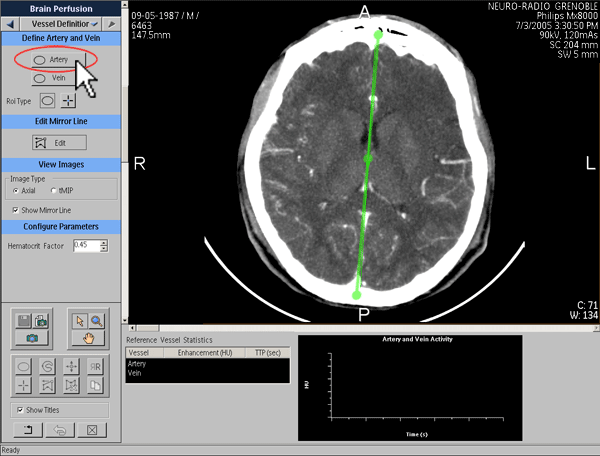

Définition de la fonction d’entrée artérielle